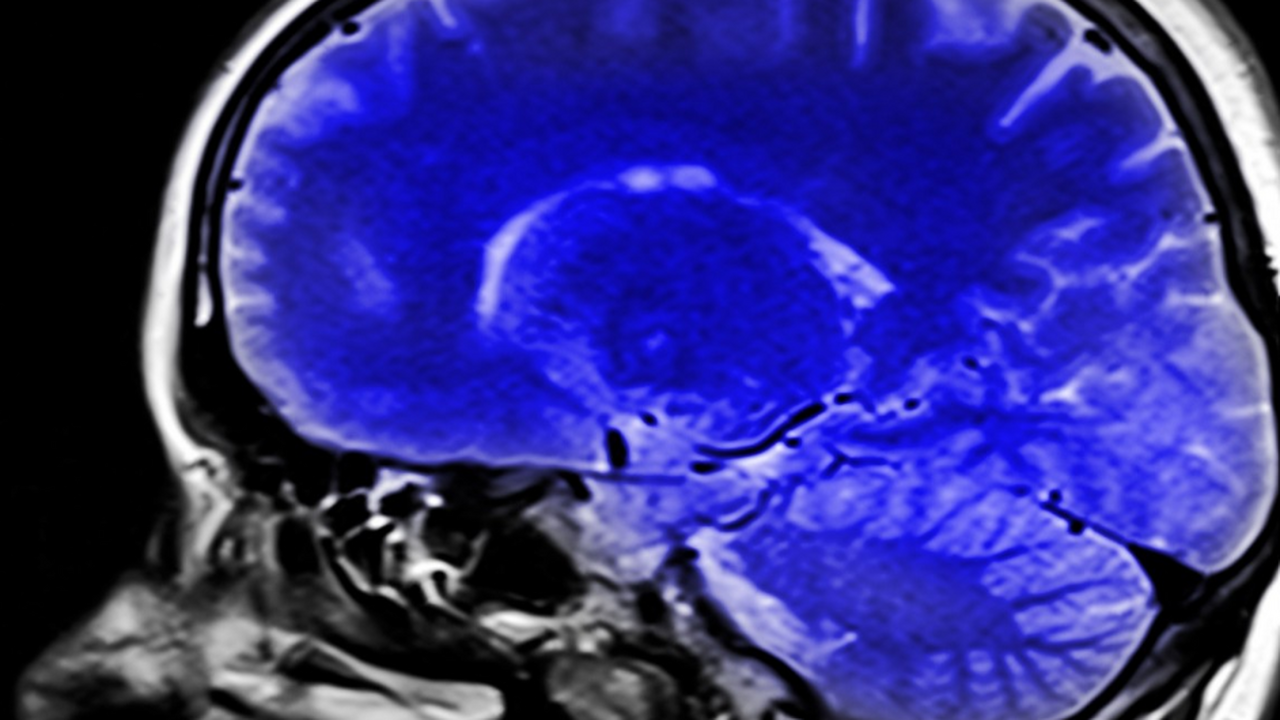

Австралийские исследователи из Сиднейского университета сделали важное открытие: в стволе мозга человека обнаружена детализированная система, которая регулирует восприятие боли в зависимости от её локализации в теле. Результаты опубликованы в журнале Nature и уже названы экспертами прорывом в нейробиологии.

С помощью МРТ-сканирования и экспериментов с эффектом плацебо учёные выявили, что различные участки ствола мозга по-разному активируются при снижении боли в разных частях тела. Ведущий автор исследования, доктор Льюис Кроуфорд, отметил:

Как установили специалисты, верхние отделы ствола мозга активнее реагируют при снятии лицевой боли, тогда как нижние отделы — при боли в руках и ногах. Это открытие опровергает прежнее представление о том, что обезболивающая система мозга работает как единый «выключатель боли». На самом деле она представляет собой высокоточно координированную структуру, способную избирательно реагировать на конкретные участки тела.